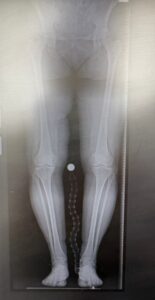

W dniu 16 stycznia 2026 r. w CSK UM w Łodzi, w Klinice Ortopedii z Pododdziałem Ortopedii Dziecięcej, został wykonany pierwszy w Europie Środkowo-Wschodniej zabieg alloplastyki połowiczej stawu kolanowego z wykorzystaniem najnowocześniejszego robota operacyjnego VELYS 🚀.

Alloplastyka połowicza stawu kolanowego